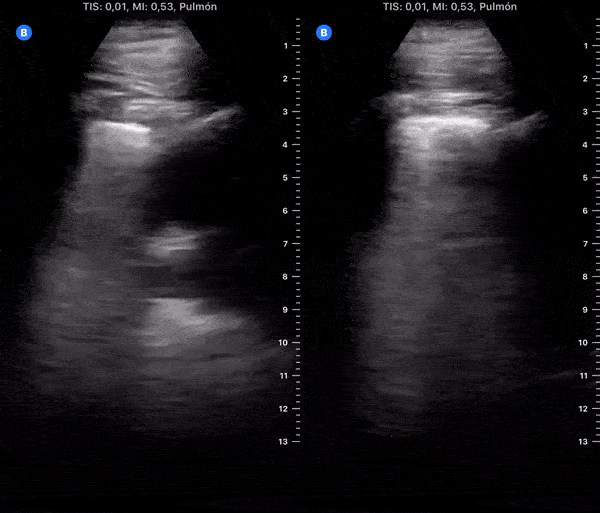

COVID 19 Lung US Disease Progression - Day 20

Day 20 after #COVID diagnosis. Almost recovered. SpO2 96%. #POCUS update: Significant improvement, remains thick pleura & B-lines. Yesterday tested NEGATIVE. I will try update a lung scan every week. FINALLY, I am returning to the TRENCHES. @yaletung